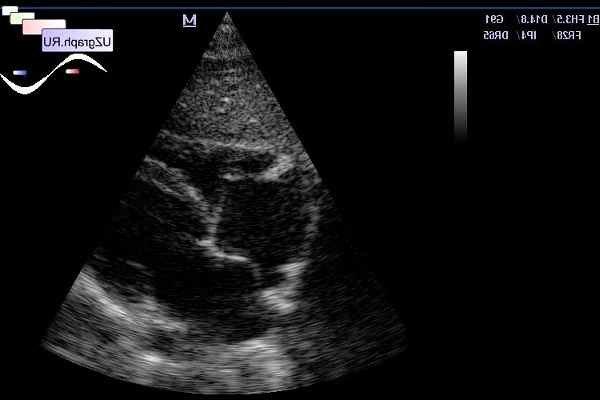

Чреспищеводная эхокардиография (ЧПЭхоКГ) – метод ультразвуковой диагностики сердца с использованием специального датчика, вводимого через пищевод. Позволяет улучшить «ультразвуковое окно» и дает возможность значительно лучшей визуализации мелких структур сердца из чреспищеводного доступа. В последние годы в клиническую практику все более активно внедряется методика трехмерной чреспищеводной эхокардиографии (3D-ЧПЭхоКГ) , представляющая интерес, в первую очередь, в кардиохирургической практике.

Современные трехмерные ультразвуковые технологии в масштабе реального времени значительно расширяют диагностические возможности метода. Методика «Live 3 D» дает непосредственное «живое» изображение в пирамидальном объеме и позволяет визуализировать клапан во множестве ракурсов, т.е. «посмотреть на анатомическую структуру с разных сторон». Таким образом, оптимизируется топическая и морфологическая диагностика сердечных структур. Программа позволяет также выполнять различные планиметрические измерения. Программа реконструкции клапана в полном объеме позволяет получить пирамидальное изображение с более широким углом (80ْ), что, в свою очередь, увеличивает количество проекций визуализации и информативность исследования. Эти программы также работают в режиме «on-line» Вышеперечисленные методики представляют большой интерес, в первую очередь, в кардиохирургической практике при реконструктивных вмешательствах на клапанах.

На трехмерном изображении нормального митрального клапана видны две створки: большая по площади передняя и задняя, переднелатеральная и заднемедиальная комиссуры. Динамическая трехмерная ЭхоКГ, показывающая клапан в движении, дает возможность судить о подвижности створок. В диастолу, при полном раскрытии створок, можно измерить площадь митрального отверстия, а в систолу – судить о коаптации створок. Преимущество 3D ЭхоКГ, по сравнению с традиционной двухмерной эхокардиографией, заключается в том, что мы имеем изображение створок и фиброзного кольца клапана по всему периметру. Это позволяет, в свою очередь, не только визуально более полно оценивать клапан, но также выполнить измерения переднезаднего и поперечного (комиссурального) диаметров ФК и определить их соотношение. Трехмерная реконструкция дает возможность также оценивать физиологическую подвижность фиброзного кольца клапана, проводя эти измерения в разные фазы сердечного цикла. Стандартные измерения (диаметр ФК, площадь митрального отверстия) осуществляются планиметрически с поправкой на глубину сканирования.